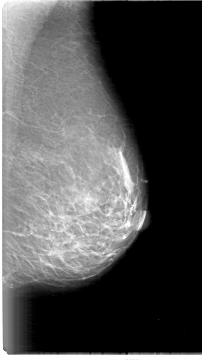

D_4001_1.RIGHT_MLO

LEFT_MLO LINES 5386 PIXELS_PER_LINE 3016 BITS_PER_PIXEL 12 RESOLUTION 43.5 NON_OVERLAY